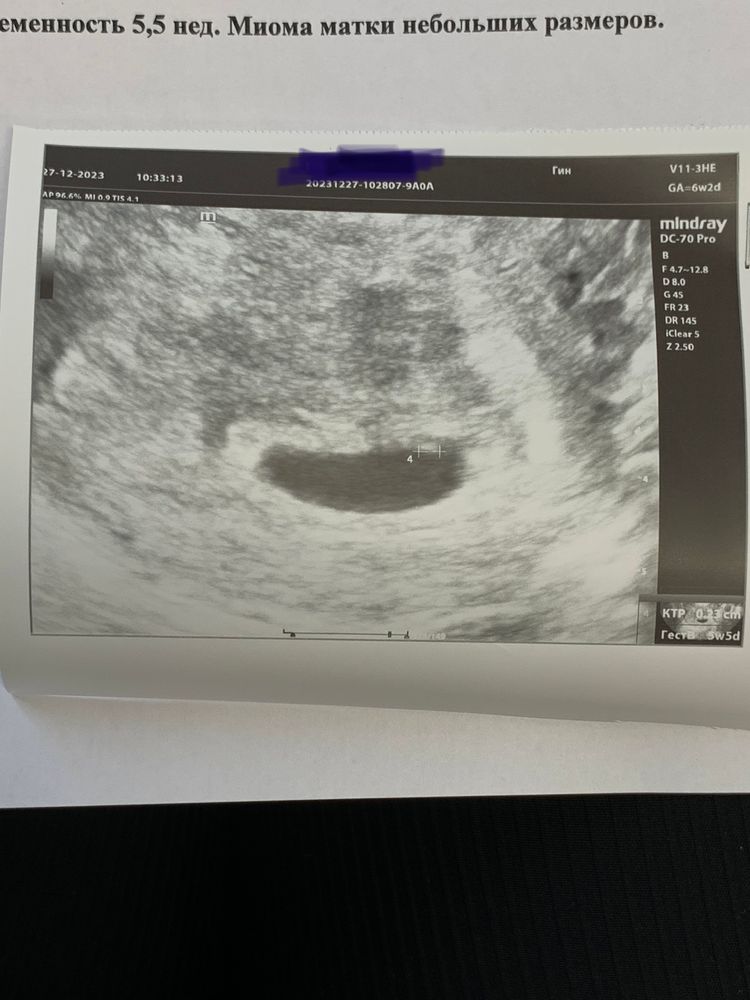

6+2 по пм. По узи 5+5 🤞🏽❤️чуть симптомов

Сердечко не слышала, но видела пульсацию, пока не полезли к нему тормошить, попозже послушаем) мой цикл 32 дня, о была на 18-19 дц, поэтому сказала врач срок такой, все в порядке 🤞🏽❣️